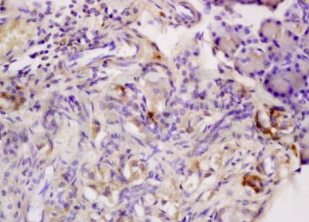

组织/细胞:大鼠胰腺组织;4%多聚甲醛固定和石蜡包埋;

抗原提取:柠檬酸缓冲液(0.01M,pH 6),15min煮沸,用3%过氧化氢阻断内源性过氧化物酶30min;37℃下阻断缓冲液(正常山羊血清)20 min;

孵育:抗脂联素受体2多克隆抗体,未结合 1:200,4°C下过夜,然后与二级抗体 结合,DAB 染色。